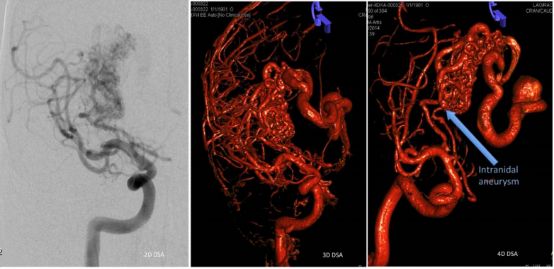

(3)脑动静脉畸形(AVMs):采用立体定向放射治疗可获得较好疗效。单次大剂量照射,可使AVMs硬化,阻止出血。对于2cm 以下的病灶效果较好,绝大部分病灶可以在2年内消失。

脑动脉血管造影